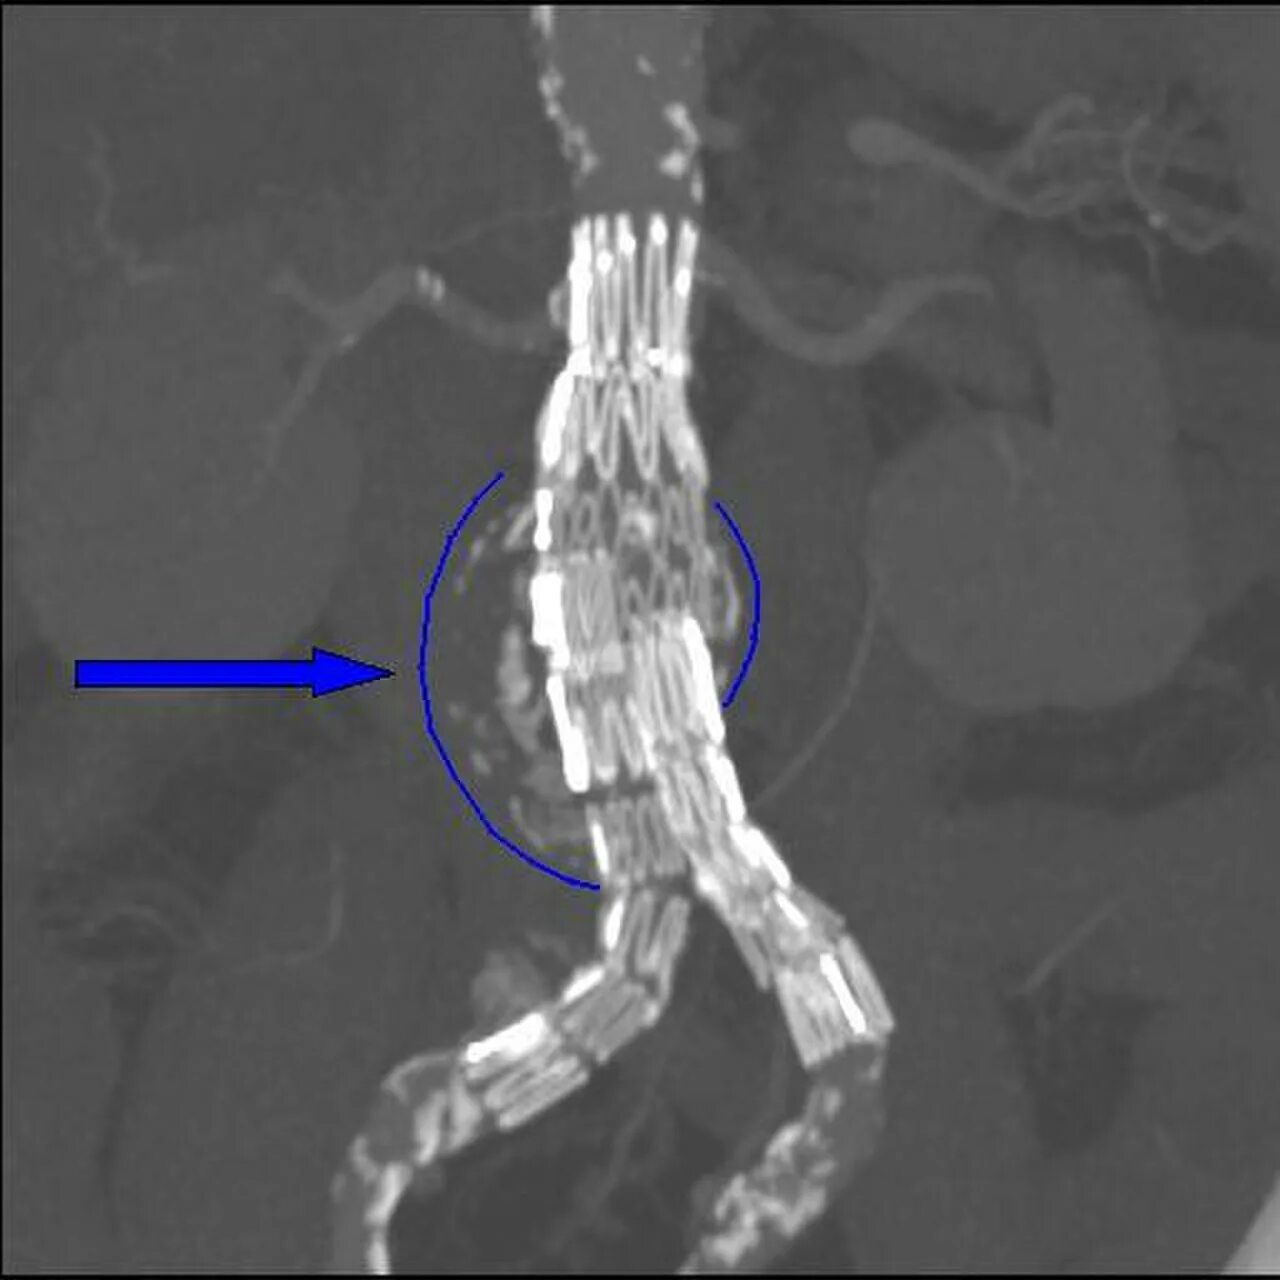

Стенты мрт